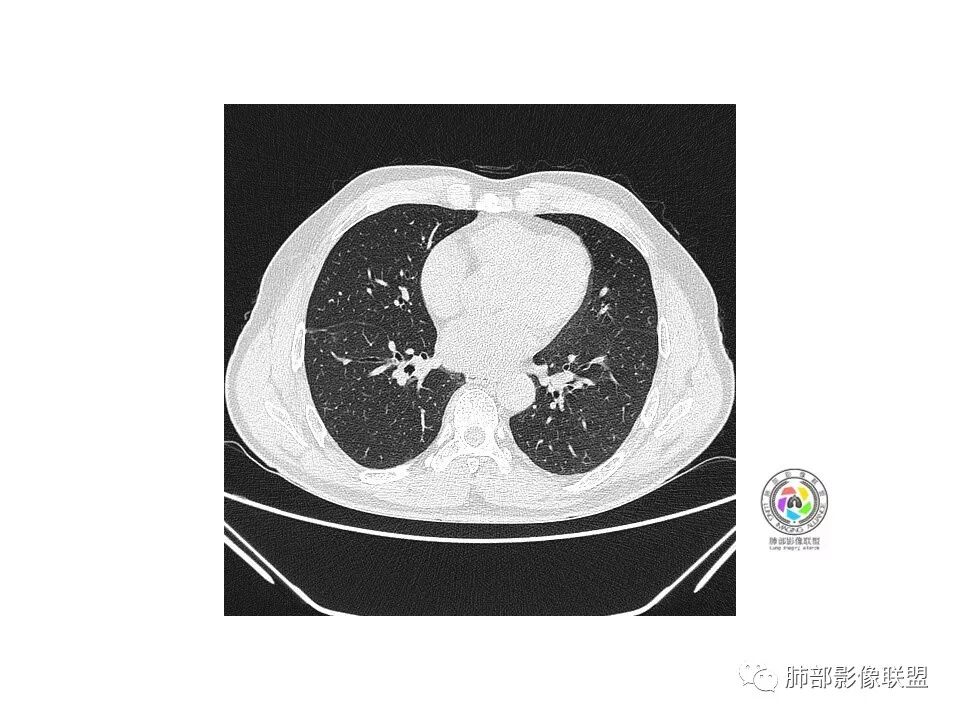

右肺下叶mGGO,边缘清晰,浅分叶,内血管影增粗,见点状实性成分,小支气管牵拉扩张,考虑MIA,建议抗炎后复查。

右肺下叶磨玻璃结节,边界清晰,边缘有分叶及月牙铲,并可见轻度胸膜牵拉,收缩力弱,有血管移动联通征,而且病灶内血管影轻度增粗,实性成分很少,考虑AIS,可以让子弹再飞一会,或常规抗炎治疗后复查。

右肺下叶前基底段磨玻璃小结节,其内血管稍增粗,边缘见分叶、月牙铲,考虑ais,炎性结节不排

有增粗,联通、移动,高度怀疑Ca,常规抗炎后复查

腺癌